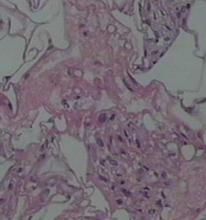

組織病理:皮下脂肪小葉間早期有中性粒細胞與單核細胞為主的炎症浸潤。晚期出現組織細胞、泡沫細胞、淋巴細胞和異物巨細胞浸潤,脂肪細胞變性、細胞內含有針狀結晶,類似新生兒皮下脂肪壞死症所見脂肪結晶,甚至可見整個腸道脂膜炎病變。